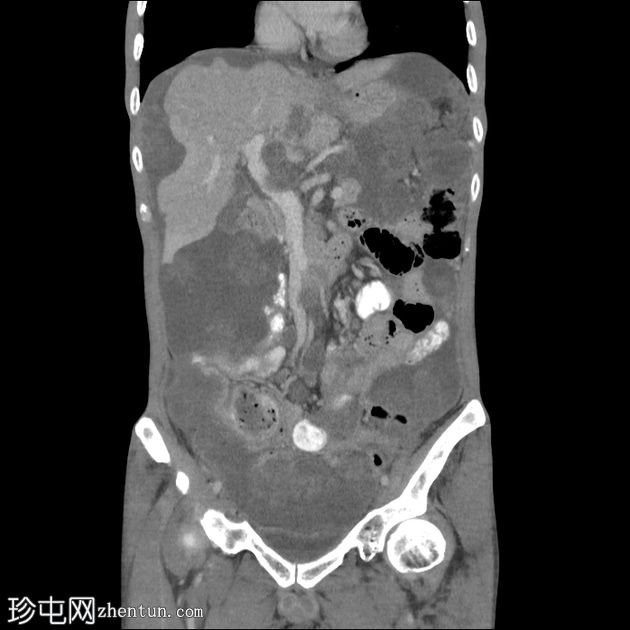

冠状位增强扫描(动脉期)

大网膜和肠系膜内可见低密度、不均匀的腹膜积液,脏器表面呈扇形凹陷,尤其以肝脏和脾脏最为明显。

阑尾肿大,长 5.0 cm,直径 1.2 cm,大小符合,可能提示阑尾黏液性肿瘤

直肠穹窿可见一处厚度 1.2 cm、长 4.0 cm 的增强壁增厚。可见病灶周围及骶前淋巴结肿大,最大者直径 1.6 cm。

可见双侧少量胸腔积液(右侧:1.0 cm;左侧:0.2 cm),右下后基底段被动性塌陷。